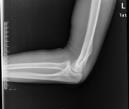

儿童陈旧性孟氏骨折

术后1个月肘关节侧位片

儿童陈旧性孟氏骨折,术前桡骨小头陈旧性脱位,经截骨矫形治疗后1个月,桡骨小头已复位,患儿肘关节屈伸功能(1-2图),前臂旋转功能(3-4图)正常